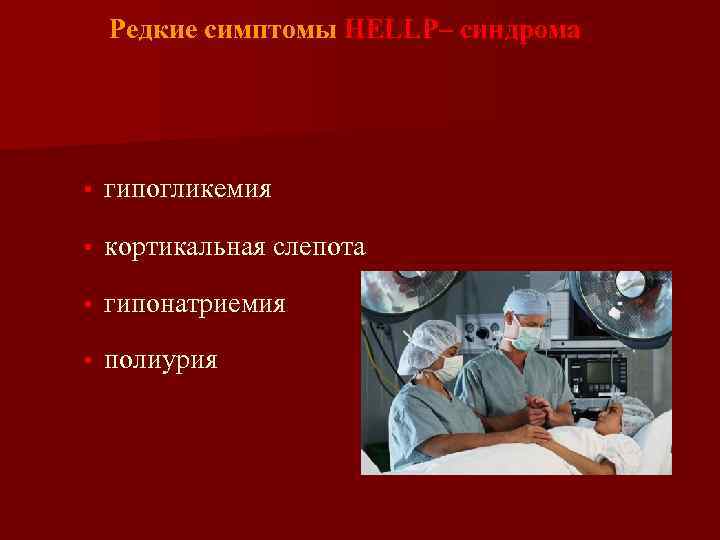

Редкие симптомы HELLP– синдрома • гипогликемия • кортикальная слепота • гипонатриемия • полиурия

Редкие симптомы HELLP– синдрома • гипогликемия • кортикальная слепота • гипонатриемия • полиурия